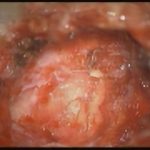

摘出 中

摘出 後